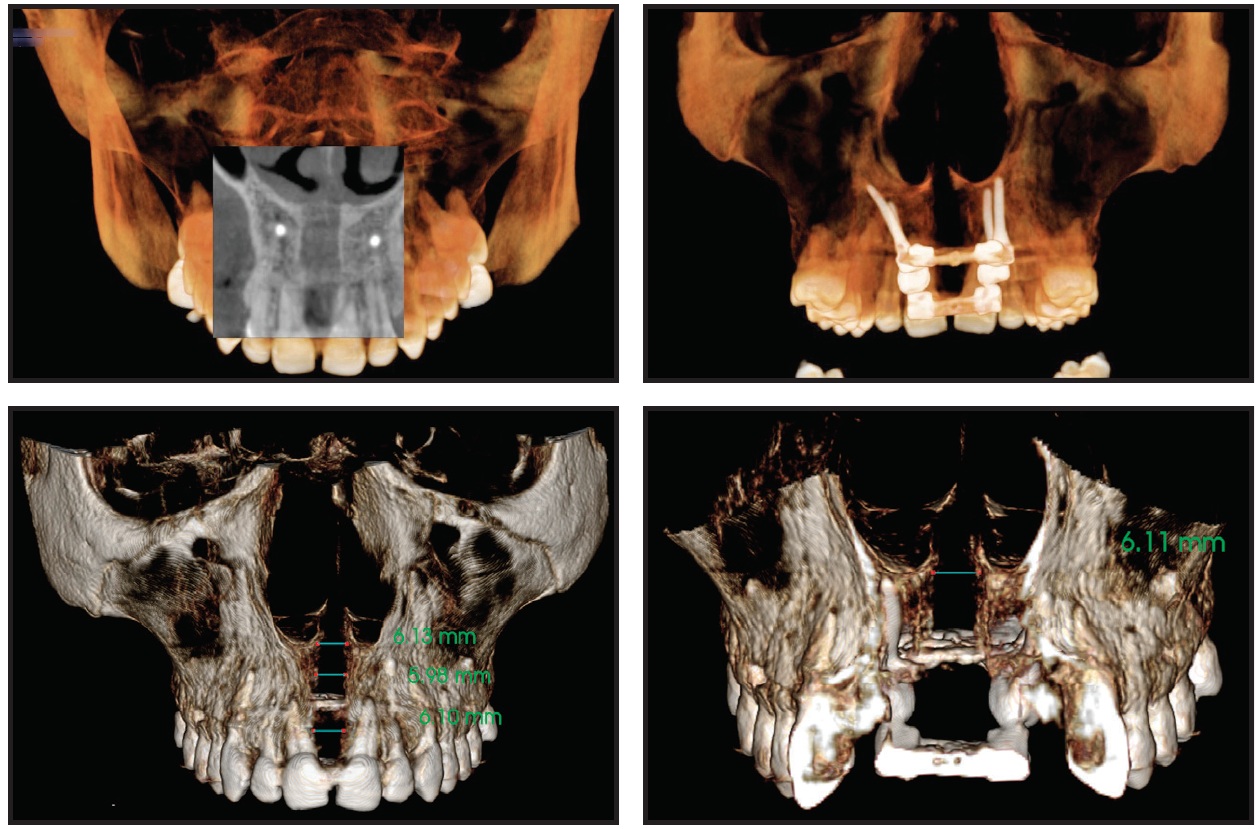

After 10 days with the second TSE, the transverse constriction and lateral crossbite had been corrected by pure skeletal expansion of the midpalatal suture (Fig. 6).

Fig. 6 Case 1. After 10 days of expansion with second expander.

The amount of expansion ranged from 7.44mm in the anterior region to 5.05mm in the posterior region (Fig. 7).

Fig. 7 Case 1. A. Anterior expansion of midpalatal suture. B. Posterior expansion.

An increased open bite was observed due to premature contact between the upper and lower third molars (Fig. 8), but no buccal tipping or molar protraction occurred (Fig. 9).

Fig. 8 Case 1. A. Before treatment. B. After expansion.

Fig. 9 Case 1. A. Before treatment. B. After first expansion. C. After second expansion. D. Superimposition of pre- and post-expansion models.

Four miniscrews (2mm in diameter) were inserted in the palatal vault: two 15mm miniscrews in the front, one 13mm miniscrew in the posterior right side, and one 15mm miniscrew in the posterior left side (Fig. 13). A TSE was placed, and the patient was instructed to perform two activations per day. The palatal expansion was completed after 21 days, when a diastema had developed between the central incisors as a result of opening the midpalatal suture (Fig. 14).

At this point, the bilateral crossbite was still present. A new impression of the upper arch was used to simulate surgical forward movement of the maxilla into a Class I canine relationship (Fig. 15). Because this diagnostic simulation showed that the transverse expansion was adequate (Fig. 16), we decided to block the TSE and proceed with surgical-orthodontic treatment. The amount of expansion ranged from 6.1mm in the anterior region to 5.71mm in the posterior region (Fig. 17). No dental or periodontal side effects were observed, nor was any buccal tipping or molar protraction (Fig. 18).

Fig. 17 Case 2. Expansion of midpalatal suture.